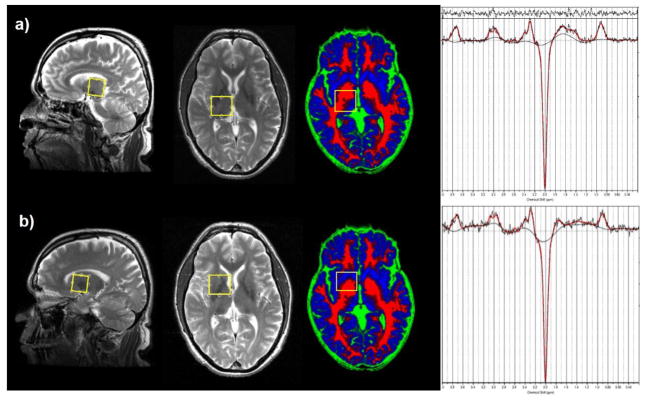

MRI and MRS exams were performed using a 3T GE Signa MRI scanner equipped with an 8-channel head coil. A high-resolution 3D T1-weighted FSPGR sequence (TR/TE=6.26/2.67 ms, resolution: 1×1×1 mm3) was followed by a fast T2-weighted sequence, acquiring sagittal and axial images aligned with the anterior and posterior commissure (AC/PC) for accurate placement of the MRS volumes of interest (VOIs). GABA spectra were acquired using the MEGA-PRESS sequence (TR/TE=2000/68 ms) (Mullins et al., 2014) with the editing pulses centered on 1.9 ppm (edit ON) and 7.5 ppm (edit OFF). 256 averages were acquired for edit ON and edit OFF spectra in an interleaved fashion. 8 averages of water reference scans without water suppression were acquired for frequency and phase correction. To determine the thalamic GABA level the MRS VOI was centered on the right thalamic region (25 mm × 30 mm × 25 mm) as shown in Fig. 2. The same GABA-edited MRS measurement was also performed on the right corpus striatal region (25 mm × 30 mm × 25 mm), which is referred to as the striatal region in this paper, including globus pallidus and a part of putamen and caudate nucleus. This VOI intentionally overlapped partly with the thalamus VOI to detect or rule out a possible influence from striatal GABA signal to the large voxel size of the thalamic VOI.

Figure 2.

Thalamus a) and striatum b) VOI for GABA measurements shown on sagittal and AC-PC aligned views on T2-weighted images, and on an axial view of a brain tissue map (red: white matter, blue: grey matter, green: CSF). Please note the tissue maps have a slightly different angulation from the AC-PC aligned T2-weighted images. Also shown are typical GABA-edited spectra from thalamus (top) and striatum (bottom) fitted with LCModel (red lines).

Edit ON and OFF spectra were first post-processed with a Matlab 2013a (The MathWorks, Natick, 2013) tool to perform coil combination, zero and first order phase correction, as well as frame-by-frame spectral alignment. Difference spectra obtained from subtracting the averaged OFF spectra from the averaged ON spectra, showing a GABA peak at 3 ppm, were quantified using LCModel V6.3-1B (Provencher, 1993). A basis set generated by density matrix simulation using GABA coupling constants from Kaiser et al. (2008) was used. The examples of GABA-edited spectra from the thalamus and the striatum fitted by LCModel are shown in Fig. 2. 3D T1-weighted images were segmented into grey matter (GM), white matter (WM) and cerebrospinal fluid (CSF) using statistical parametric mapping (SPM8, Wellcome Department of Imaging Neuroscience, London, United Kingdom). The percentages of GM, WM and CSF for each VOI were then calculated from the tissue probability maps with a home-made Matlab (The MathWorks, Natick, MA) code. Since CSF has a near-zero concentration of GABA and other metabolites, GABA levels were corrected for CSF to obtain tissue GABA concentrations. Examples of tissue maps of GM, WM and CSF overlaid with the GABA VOIs are shown in Fig. 2. A widely-used approach in the MRS literature expressed by the following equation (Chowdhury et al., 2015) was applied to obtain the CSF-corrected tissue GABA levels from each VOI: